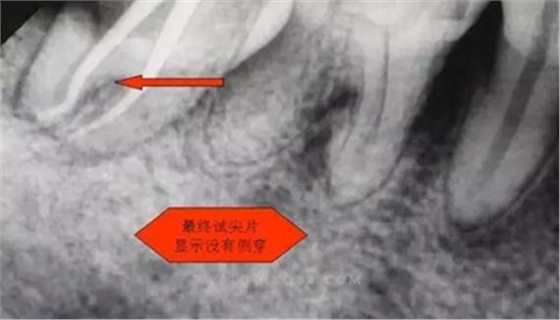

圖四

開髓完后,總覺得是不是牙體量去多了,拍片給人這種直觀感覺。

1.拍片基本可以確定遠(yuǎn)中頰側(cè)根管是一個融合根管,也就是常見的C型根管,粗大的根管口是扁形,根管同樣呈扇貝型,根尖孔粗大。而且在根管中上段較粗大,插針拍片后遠(yuǎn)中顯示根管有側(cè)穿的可能,但是通過內(nèi)窺鏡顯示是沒有任何側(cè)穿點(diǎn),也沒有滲血和患者有疼痛現(xiàn)象。這個病例告訴我們,有時候做根管治療,為了把根管做通和預(yù)備到位,必要的牙體組織去除是可以的,后期可以用冠修復(fù)來彌補(bǔ),如果不去除,本病例的根管治療,根充時可能會面臨充填不嚴(yán)密,從而導(dǎo)致根管治療的失敗,這是不可取的。